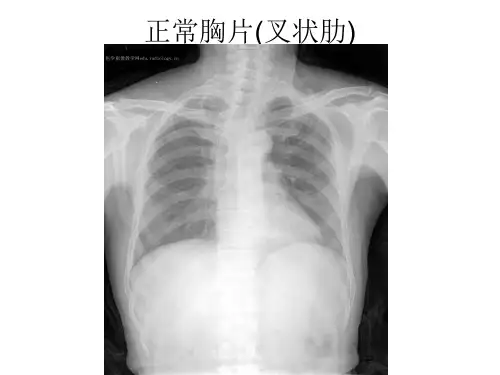

关于肺部炎症的X线表现【关键词】肺部炎症 X线(一)大叶性肺炎[图像特征]X线正位胸片:(1)左上肺可见大片高密度影,密度均匀;(2)病灶边界欠清楚。

[临床提醒] X线胸片及CT均可用于大叶性肺炎的诊断,胸片较CT在临床的应用更为广泛。

大叶性肺炎典型的影像表现为累及整个肺叶或肺段的实变影,受累肺叶或肺段的体积不缩小,内可见“含气支气管征”。

大叶性肺炎早期在X线上缺乏特异征象,部分可表现正常。

影像检查大叶性肺炎的影像学表现多样,X线胸片和CT扫描是最常用的影像学检查方法。

X线胸片在X线胸片上,大叶性肺炎的表现为局部肺实质密度增高,其轮廓模糊,可出现肺门阴影。